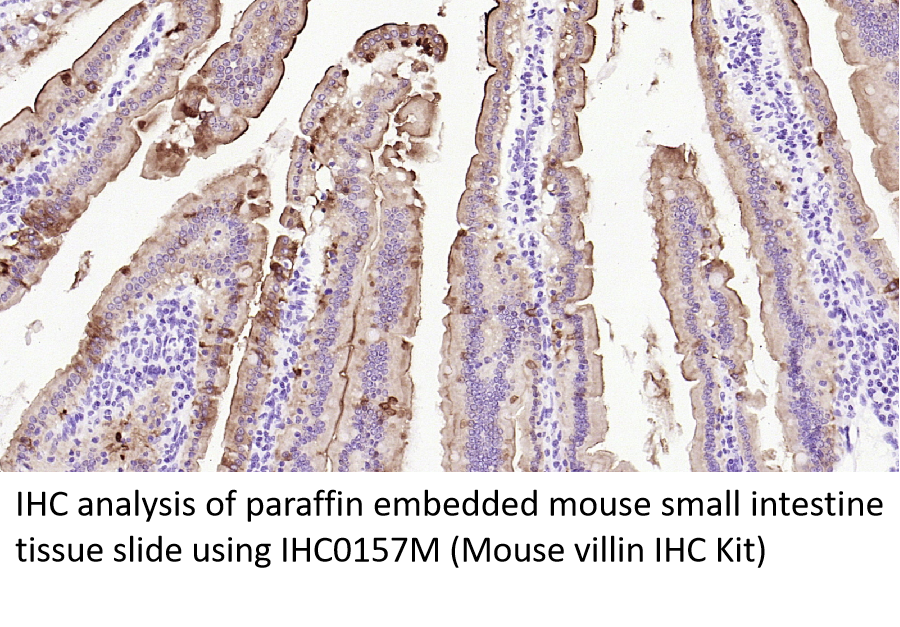

Villin

绒毛蛋白(Villin)是一种actin结合蛋白,在肠上皮细胞表达,调控结直肠癌的上皮-间质转化(EMT),也参与上皮细胞微绒毛的维持,在结直肠腺癌中阳性率达93%,癌细胞胞质弥漫强(+)伴刷状缘着色加重[14]。研究表明,Villin表达缺失是低分化结肠癌的一个特征,尤其是微卫星不稳定(MSI)肿瘤,并与生存率低有关[14]。

IHC染色定位:细胞质。